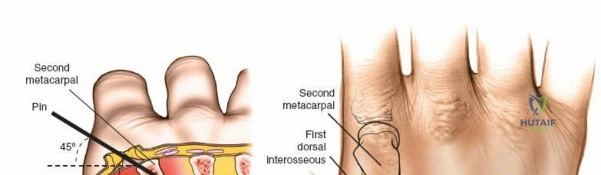

Wrist and Metacarpal Safe Zones

For spanning wrist fixators, distal pins are placed in the second metacarpal. The safe zone is the dorsoradial aspect of the second metacarpal base and shaft. The first dorsal interosseous muscle and extensor tendons must be respected. The radial artery courses proximally in the anatomic snuffbox and must be avoided during basal metacarpal pin insertion.

Metacarpal Pin Placement

1. Make two 1 cm incisions over the dorsoradial aspect of the second metacarpal.

2. Dissect bluntly, protecting the dorsal sensory branches of the radial nerve and the extensor tendons.

3. Place the tissue sleeve at a 45-degree angle to the dorsal and lateral planes to maximize purchase in the metacarpal shaft.

4. Pre-drill and insert two 3.0 mm pins.